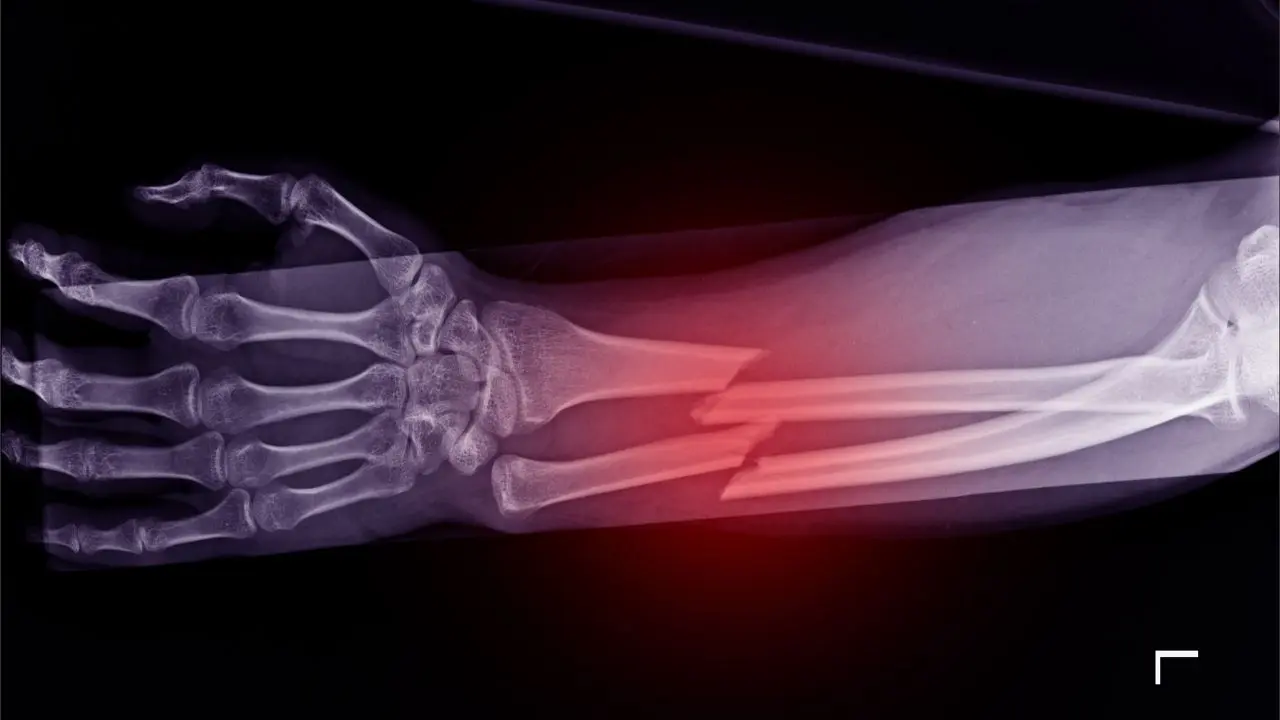

Çin’in doğusundaki Zhejiang eyaletinde bir araştırma ekibi, kemik kırıklarını yalnızca 3 dakikada tedavi edebilen yeni bir tıbbi buluş geliştirdi. “Bone-02” adı verilen bu kemik yapıştırıcısı, kırık parçaları hızlıca birleştirip sabitleyebiliyor. Bu gelişme, ortopedi cerrahisi alanında bilimsel bir atılım olarak nitelendiriliyor (NDTV & Global Times aktarımları).

Yeni geliştirilen yapıştırıcı, kanlı ortamlarda bile hızlı ve hassas sabitleme imkânı sunuyor. Ayrıca vücudun doğal süreçleriyle emilerek iyileşmeye katkı sağlıyor. Böylece geleneksel yöntemlerde olduğu gibi ikinci bir ameliyatla plaka ya da vidaların çıkarılmasına gerek kalmıyor.